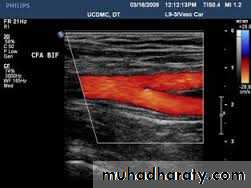

Doppler ultrasoundDuplex ultrasound

Duplex ultrasound